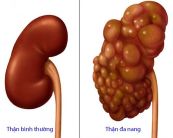

Bệnh thận đa nang là một rối loạn di truyền gây ra nhiều u nang trong thận. U nang thận là một túi bất thường chứa đầy chất lỏng, có thể làm thận phình to, thay thế gần hết các các chức năng của thận, dẫn đến bệnh thận mạn tính và giảm chức năng thận theo thời gian. Để hiểu rõ hơn về bệnh lý này, mời các bạn tham khảo bài viết dưới đây!